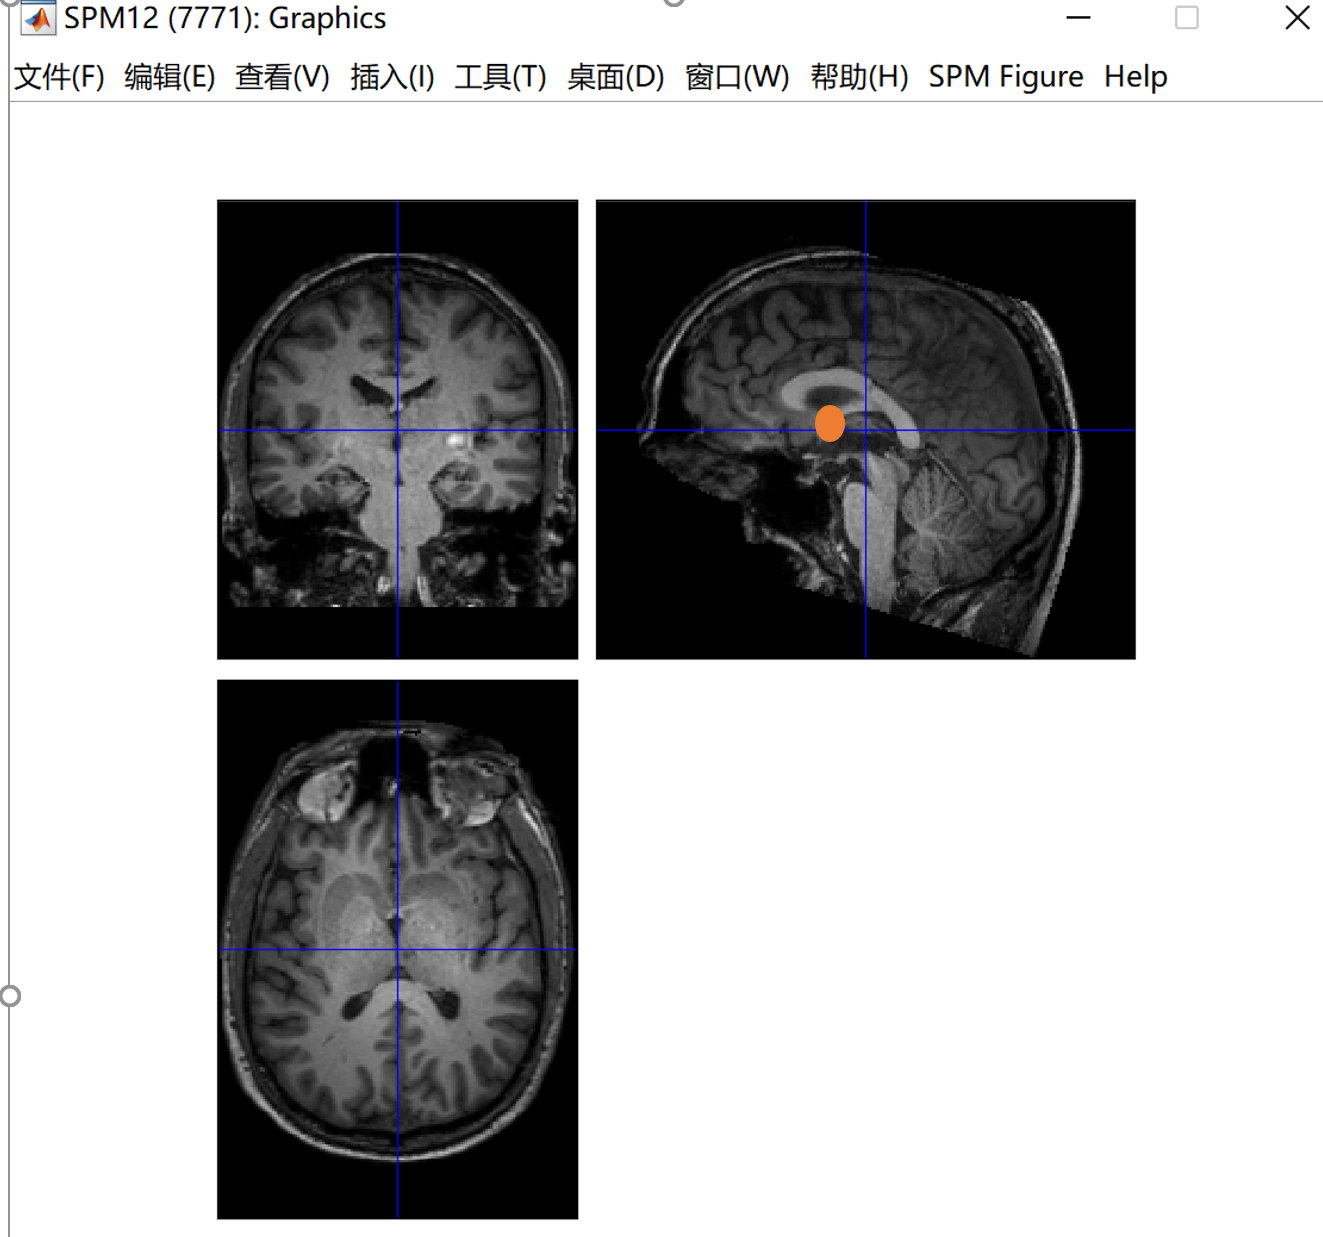

一个这样的页面,我们可以看到一个蓝色的十字线,这个线的交叉点就是我们要调整的地方,手动将交叉点放在大概下图这个位置(就是前联合的位置),前联合的位置怎么确定可以去查一下,网上有很多教程。我的理解就是大概在下图这个红色的圆里。点一下set origin之后就会出现坐标位置。然后一定要点击一下Reorient,才算是调整成功了。在这里插入图片描述在这里插入图片描述